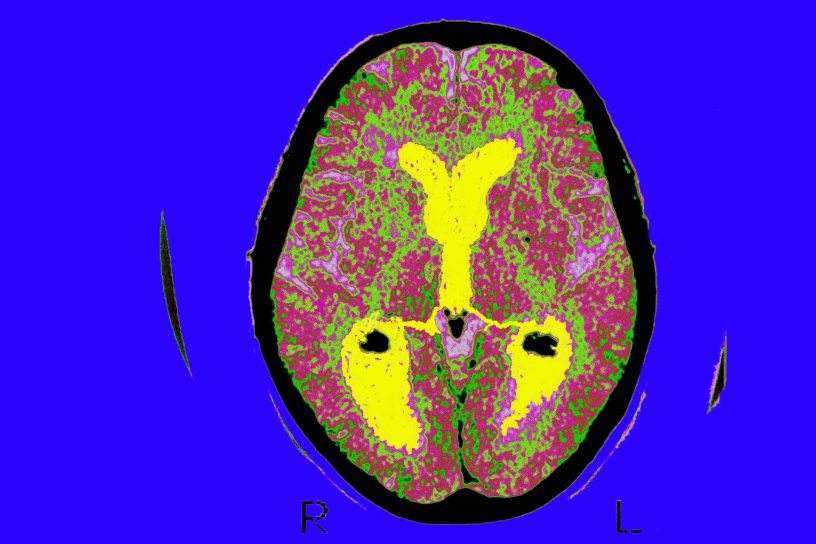

Twenty-four years later, between 2011 and 2013, a cohort of 1,633 of the original participants had MRI brain scans. They also underwent memory testing using the delayed word recall test, which asks subjects to memorise 10 words and repeat them a short time later.

The researchers found that higher inflammation scores on the baseline tests were associated with reduced size of various brain regions showing up on MRI.